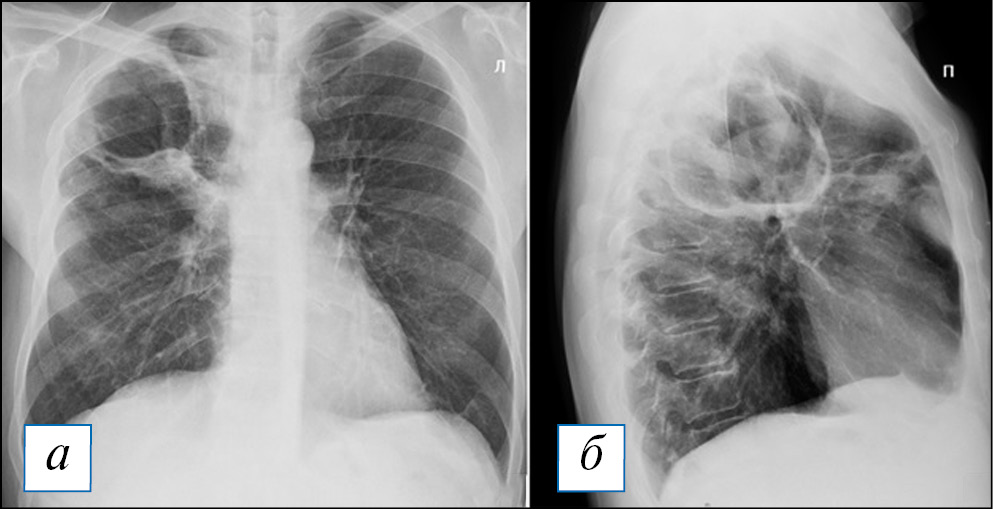

Диагностика острого абсцесса легкого по данным рентгенографии после его частичного опорожнения не представляет сложности: это кольцевидная тень с уровнем жидкости, контуры «кольца», обычно достаточно четкие (рис. 6). При рентгеноскопии или повороте тела можно наблюдать и изменение уровня жидкости в абсцессе (рис. 7). Сложнее с диагностикой абсцесса при его формировании, когда затенение не имеет типичных черт и может быть неправильной формы: оно представлено чаще круглой тенью или отграниченным затенением, центральные отделы которого могут быть несколько неоднородными, однако этот признак очень непостоянный.

Рис. 6. Рентгенография органов грудной клетки в прямой и правой боковой проекциях. Острый абсцесс в верхней доле правого легкого. В верхней доле справа имеется кольцевидная тень с небольшим горизонтальным уровнем жидкости, что свидетельствует о почти полном дренаже абсцесса. В S3 рядом с полостью — неоднородное затенение и сгущение легочного рисунка. [Изображения из архива авторов]. / Fig. 6. Chest X-ray. Acute abscess in the upper lobe of the right lung. In the upper lobe on the right there is a ring-shaped shadow with a small horizontal level of fluid, which indicates almost complete drainage of the abscess. In S3, next to the cavity, there is a non — uniform shading and thickening of the pulmonary pattern. [Images from the authors’ archive].

Рис. 7. Рентгенография органов грудной клетки в прямой и правой боковой проекциях. Острый абсцесс в верхней доле правого легкого. Полость в верхней доле справа на 1/3 заполнена жидкостью с горизонтальным уровнем, который соответствует положению пациента во время снимка (стрелки). [Изображения из архива авторов]. / Fig. 7. Chest X-ray. Acute abscess in the upper lobe of the right lung. The cavity in the upper lobe on the right is filled with liquid by 1/3 with a horizontal level that corresponds to the position of the patient during the image acquisition (arrows). [Images from the authors’ archive].